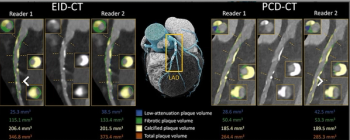

Ultra-high spatial resolution with photon-counting CT facilitated a 33 percent reduction in the assessment of median total plaque volume and a 45 percent higher inter-reader agreement for evaluation of low-attenuation plaque volume in contrast to energy-integrating detector (EID) CT.